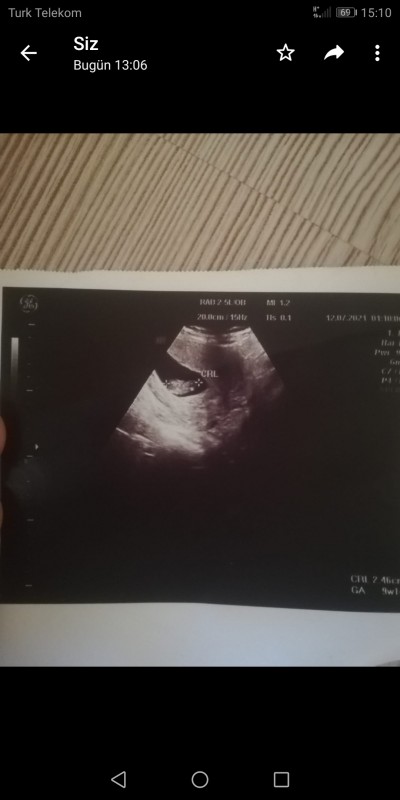

Dun sekile gore cinsiyet  soyle işiydi merak ettim luyfen lınc etmeyin saglıklı olsun onemlı olan bu ama  kırıcı olmayın

Kac haftalık diye sorsaydınız ınsan gibi derdim 12 hafta    cinsiyet ı belli bu ayda

Kesin yorum için kesenin dikdörtgenler prizması olması lazım, bu şekil bilemeyiz. Tövbe estağfurullah ya :))

doktorun cihazi bastirmasina gore kesenin sekli degisiyor aslinda...